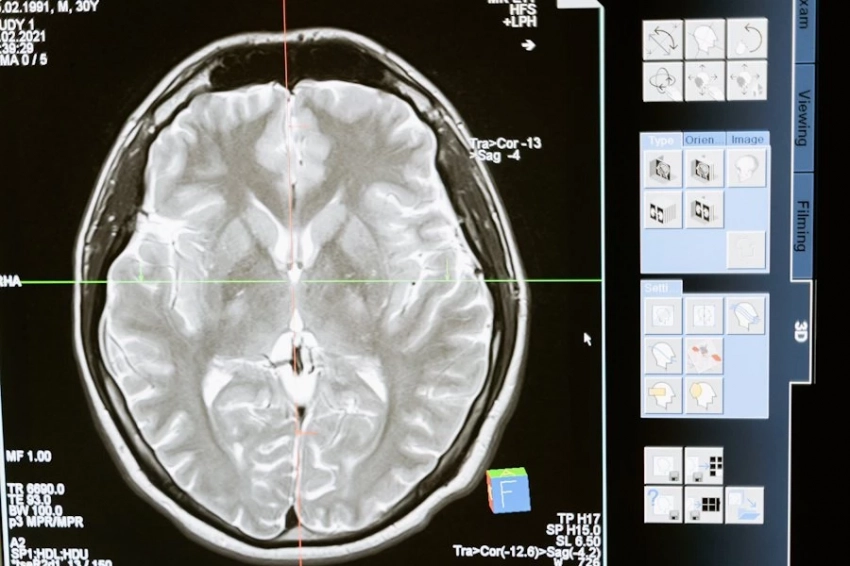

Известно, что режиссера госпитализировали 27 декабря 2024 года. С тех пор он не приходил в сознание. У Кеосаяна наблюдаются давние проблемы с сердцем - в 2008 и 2010 годах продюсер перенес два инфаркта. Супруга режиссера подчеркнула, что тяжелее всего сейчас матери Кеосаяна, которая два года назад уже потеряла одного сына.